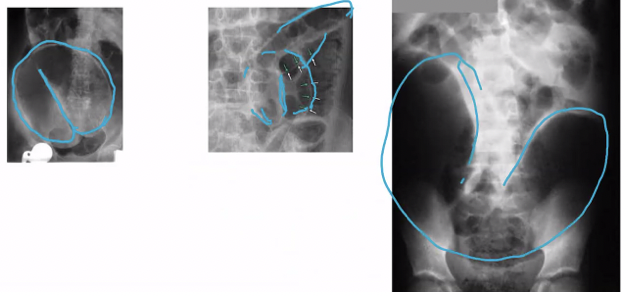

Qué es en esta Rx

Signo de grano de café